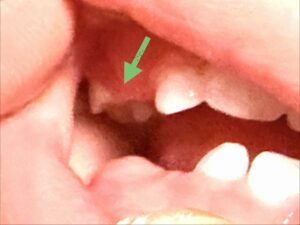

これまで上の前歯が4本、下の前歯が3本生えてきていましたが、今月に入って1本遅れていた左下の2本目の前歯(左下B)が見えてきました。

右下が順調にニョキニョキと生えてきていたのに対して、少し遅れ気味な左下B。ここから追い上げを見せてしっかりと右下と同じくらいにまで生えてくるのかどうか経過をしっかり確認して、今後のブログでもお伝えしていきます👍

そして、今月新たに生え始めた乳歯が2本ありました。

上の2本目の前歯(左右上のB)から1本分程度の隙間を空けて、奥の方に左右同時に見えてきたのは前歯から3本目を飛ばして、4本目に位置する第一乳臼歯(D)。

そして、今回生えてきた上の左右の2本の乳歯は、上顎 D|D (第一乳臼歯) 。

つまり、前から数えて3本目にあたる、大人の犬歯(糸切り歯)にあたる<C>(乳犬歯)を飛ばして<D>が生えてきたということになります。